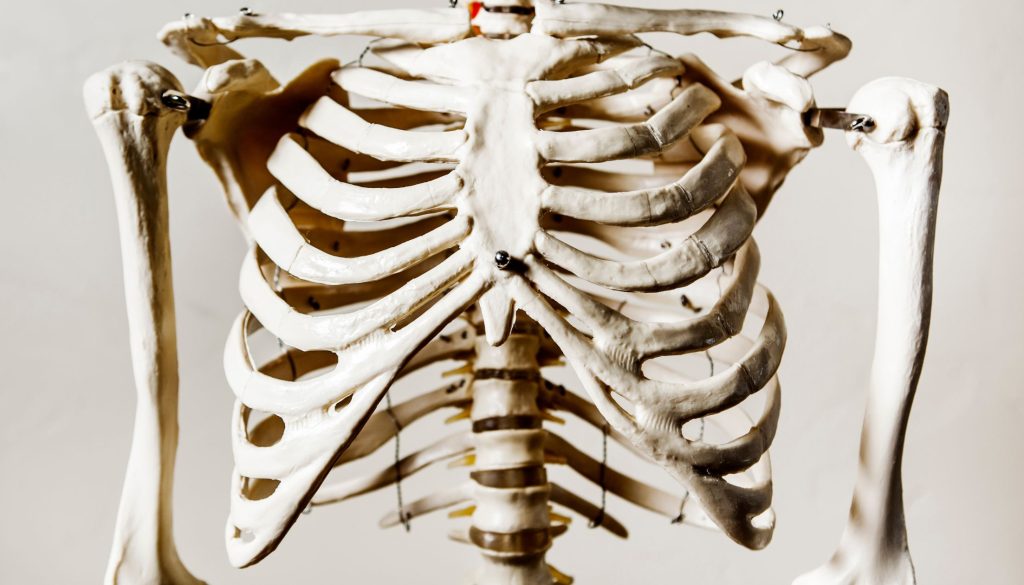

دليل شامل للنصائح والتوجيهات التفصيلية حول جراحات القفص الصدري

تعتبر جراحات القفص الصدري من العمليات الطبية الكبيرة التي قد تؤدي إلى تحسين جودة الحياة بشكل ملحوظ للأفراد الذين يعانون من مشاكل صحية خطيرة. ومع ذلك، يمكن أن يكون للعمليات الجراحية تأثيرات كبيرة على الجسم والعقل، مما يجعل من الضروري فهم الإجراءات والنصائح المناسبة لضمان التعافي بنجاح.

فهم جراحات القفص الصدري

تتضمن جراحات القفص الصدري العديد من الإجراءات مثل جراحة إزالة الأورام، تصحيح التشوهات، أو إصلاح الإصابات النّاجمة عن الحوادث. باختلاف السبب، تتطلب جميعها اهتمامًا دقيقًا من الجراح والطاقم الطبي بالإضافة إلى التزام المريض بتعليمات ما قبل وما بعد الجراحة لتحقيق أفضل النتائج.